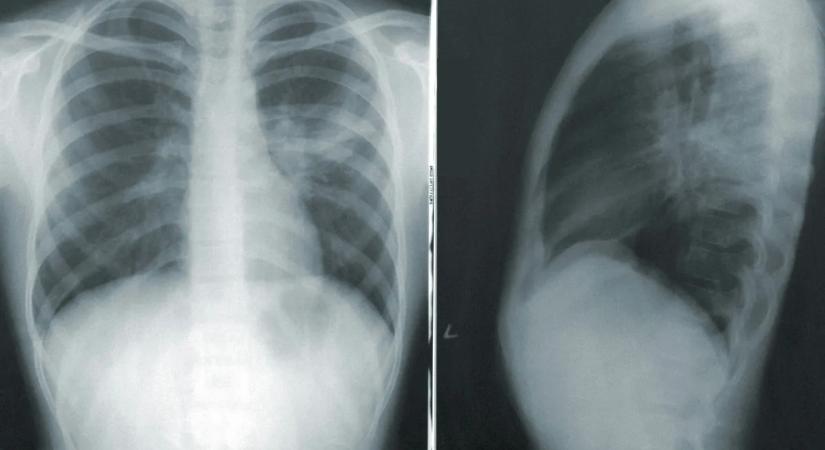

„Arra gondoltam, meg fogok halni” – soha életében nem dohányzott egy nő, mégis rákot találtak a tüdejében